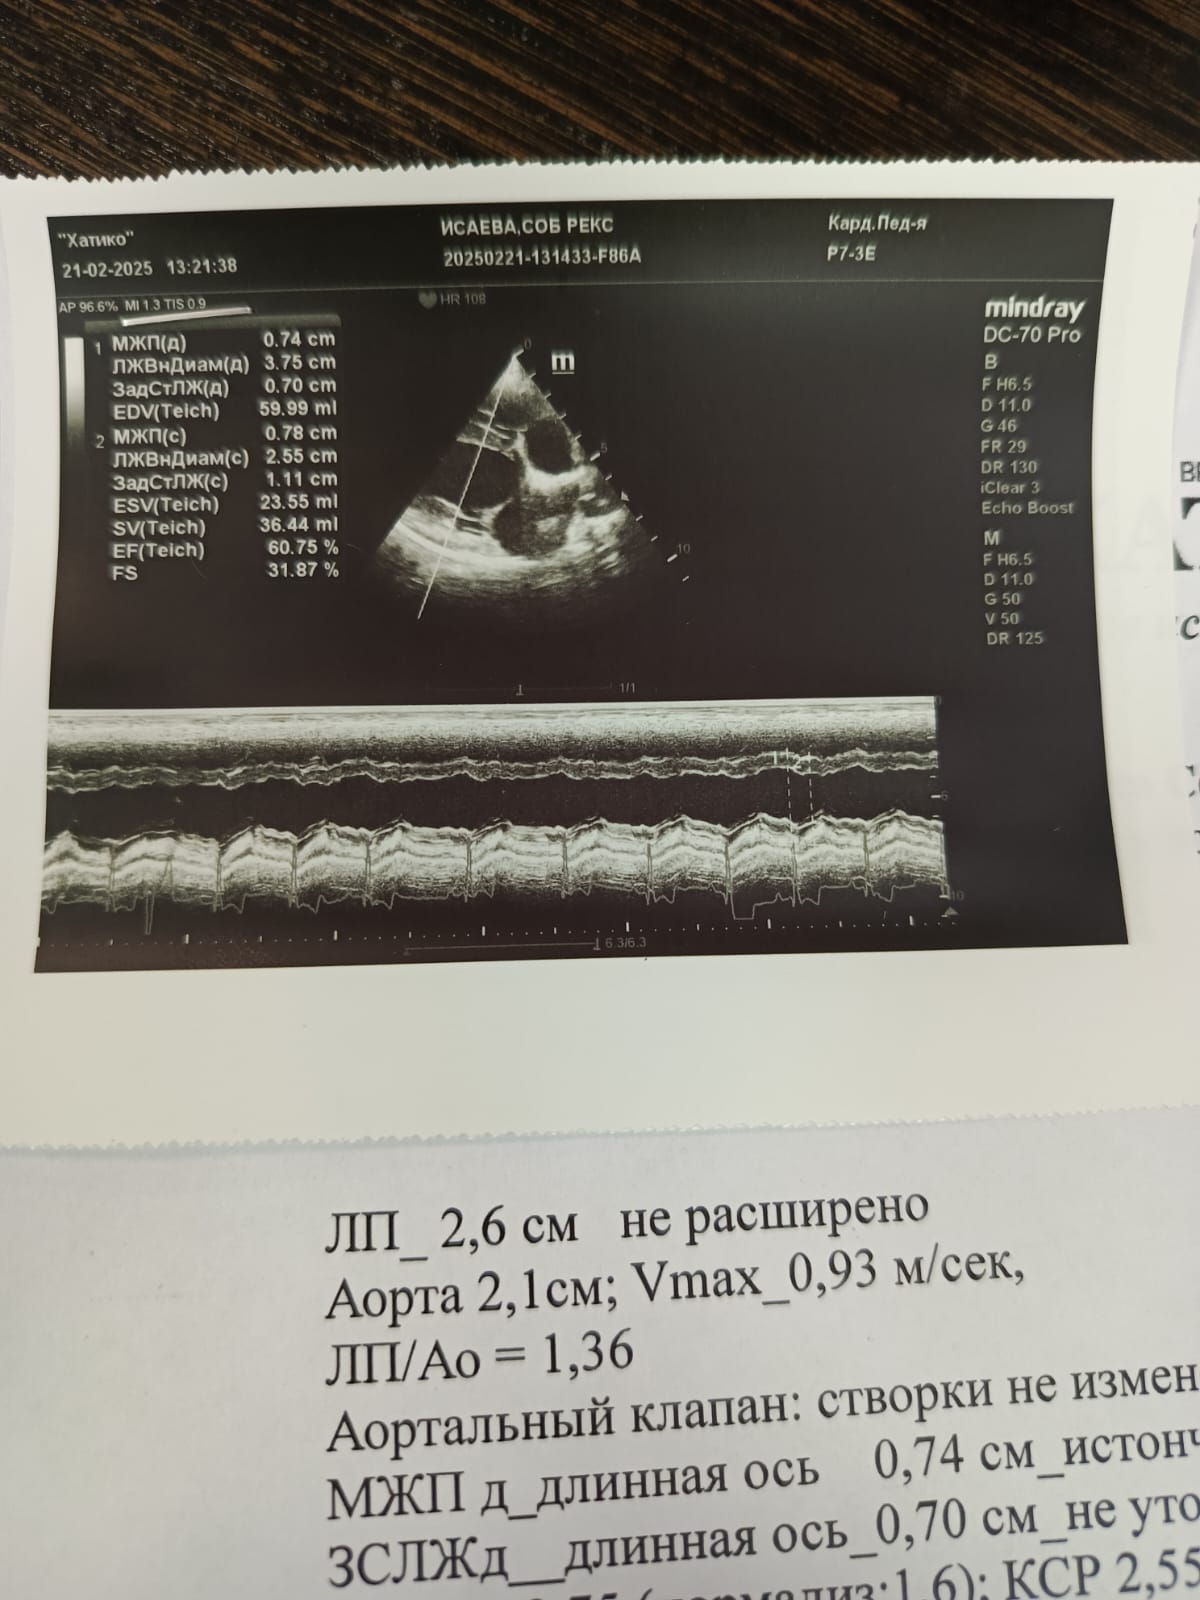

Сердце и почечные показатели

Вложения

IMG_20250221_120409.jpg

IMG-20250221-WA0008.jpg

IMG-20250221-WA0009.jpg

IMG-20250221-WA0010.jpg